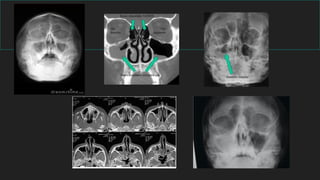

SENOS PARANASALES

Son cavidades aéreas que están en comunicación con las

fosas nasales y situadas en los huesos colindantes.

La mucosa que lo reviste se continua con la de las fosas

nasales a través de los orificios de drenaje de los senos

en la cavidad nasal.

* S. Frontales situados en el hueso frontal

* S. Etmoidales

* S. Esfenoidal

* S. Maxilares